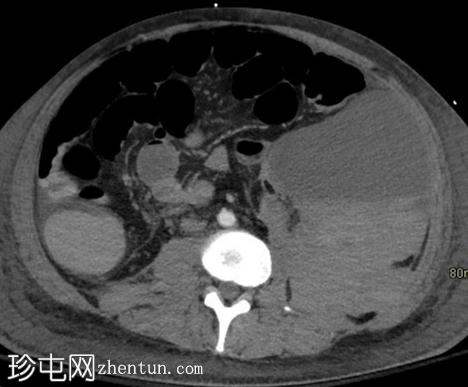

融合

轴向

冠状融合 SPECT-CT 图像显示左下腹血肿内有多个红细胞外渗灶。

轴向融合 SPECT-CT 图像证实血肿内存在标记红细胞,从而确认存在活动性出血。